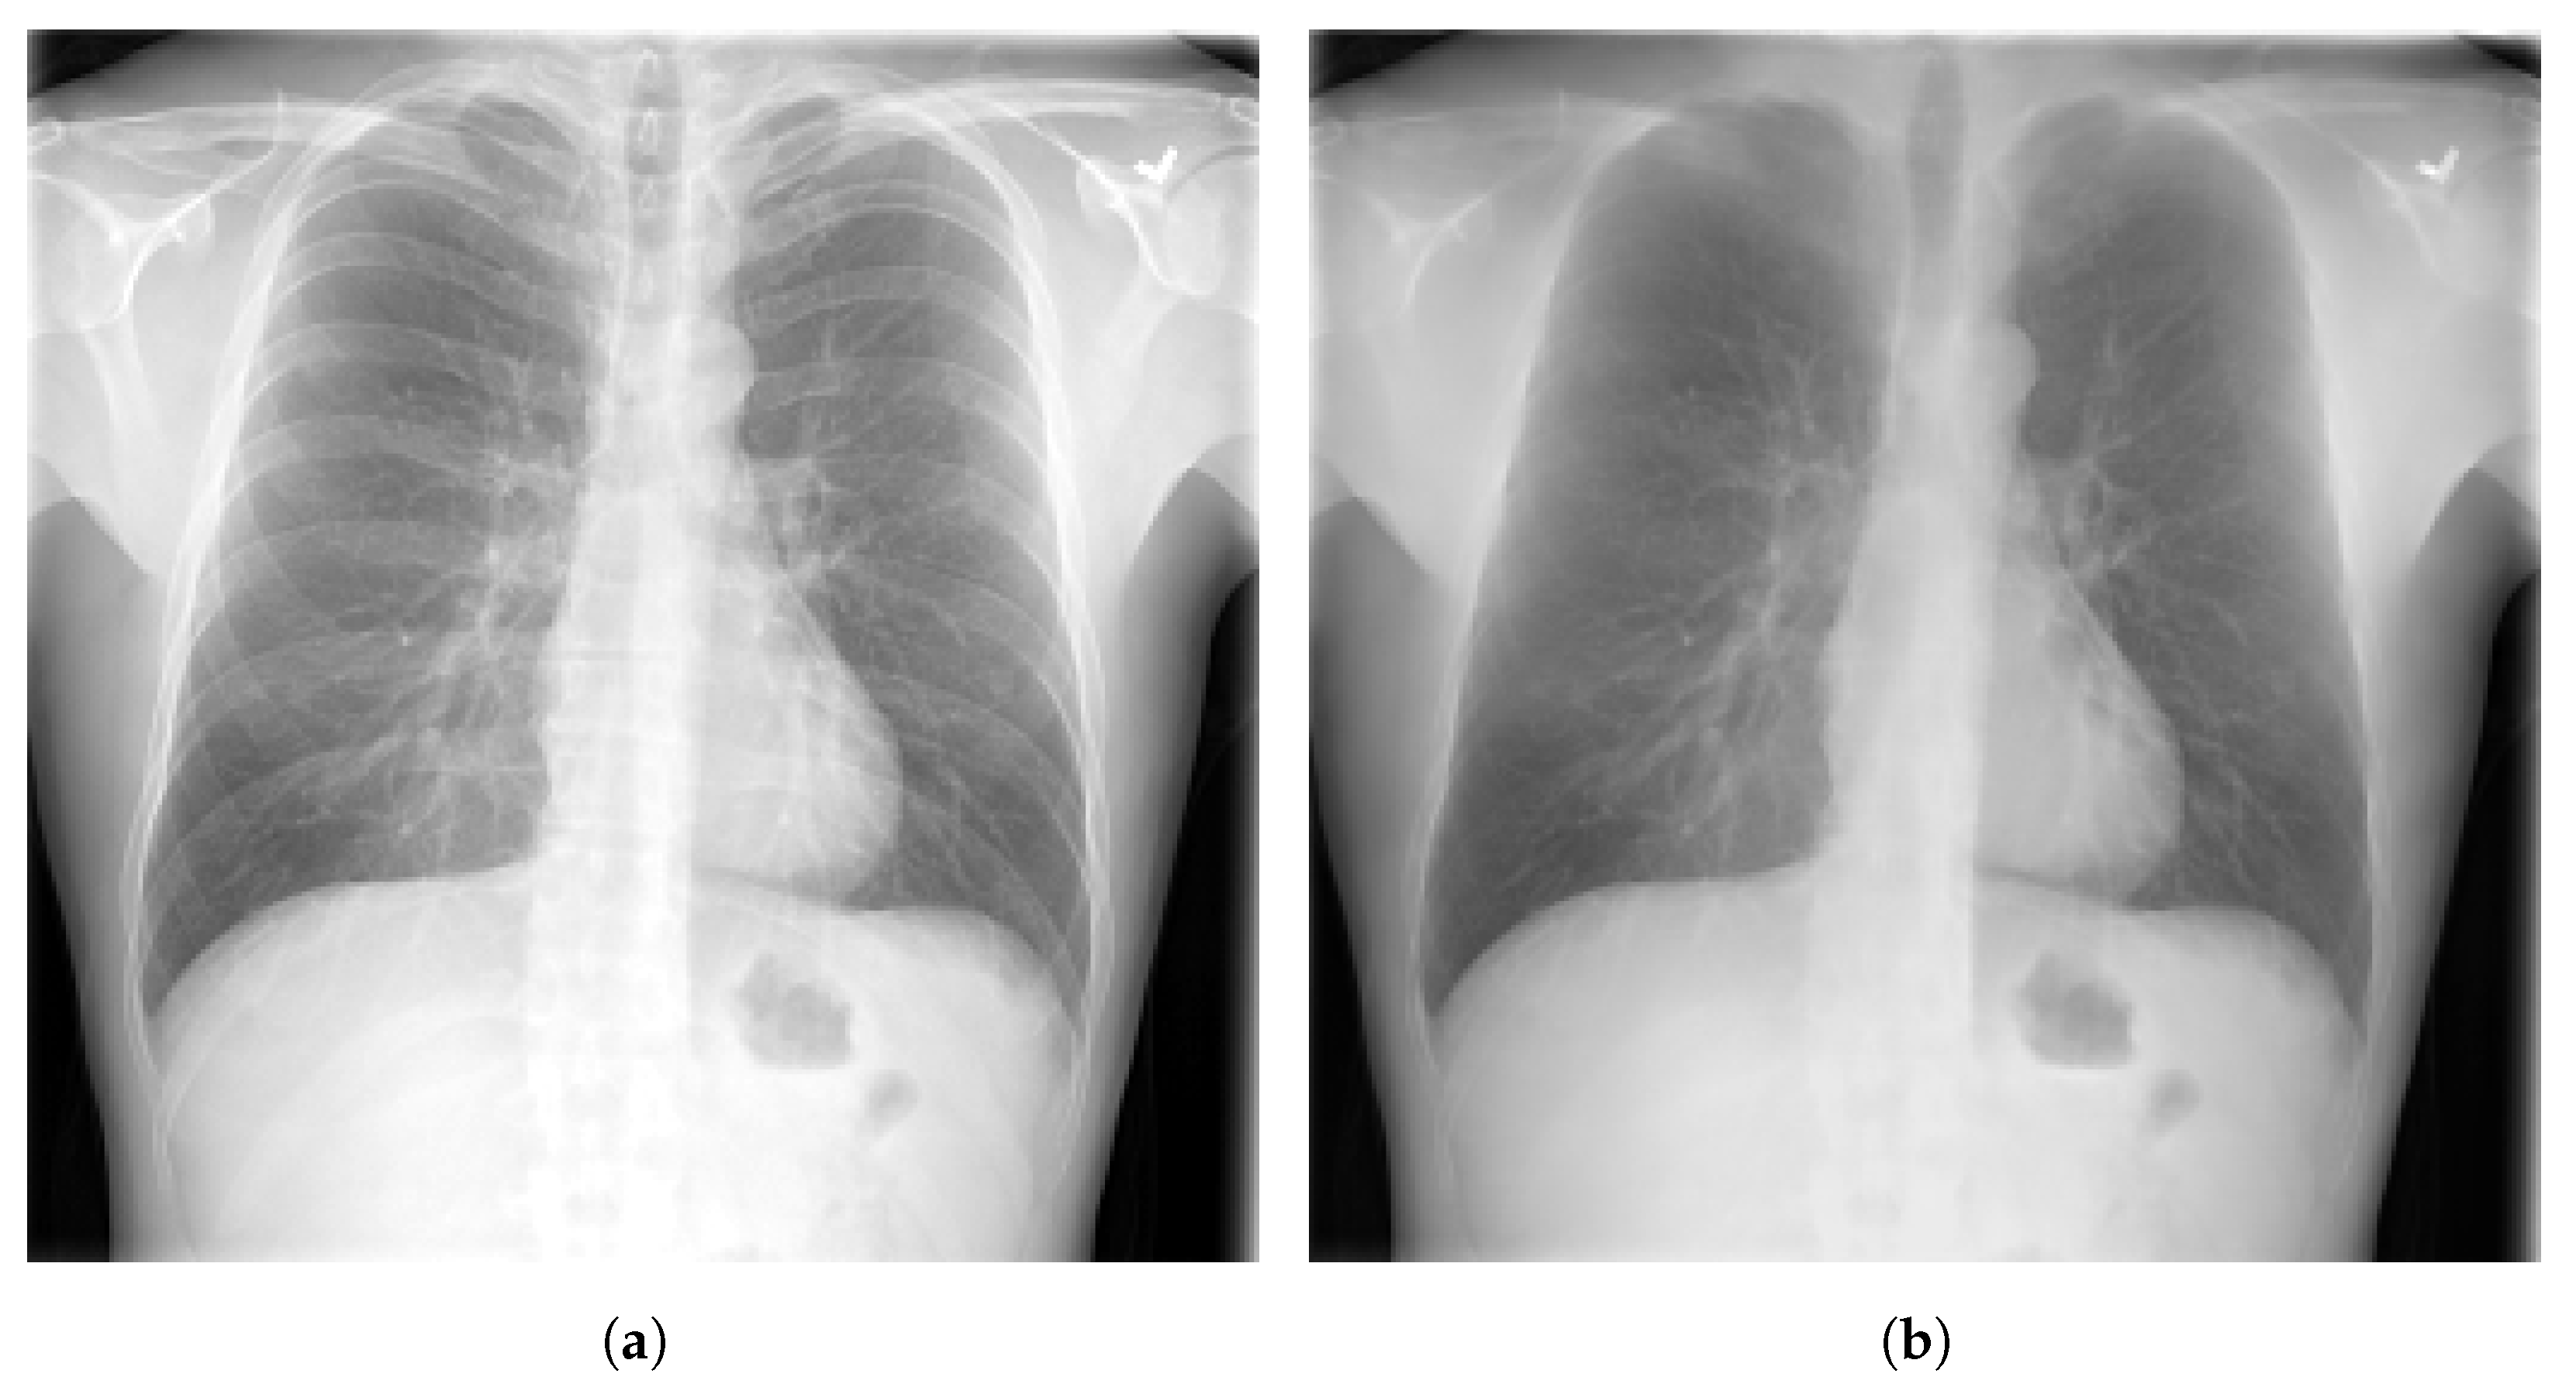

Figure 3.

Samples of CXR images from CheXpert dataset [44] where, (a) Atelectasis; (b) Cardiomegaly; (c) Edema; (d) Pneumonia.